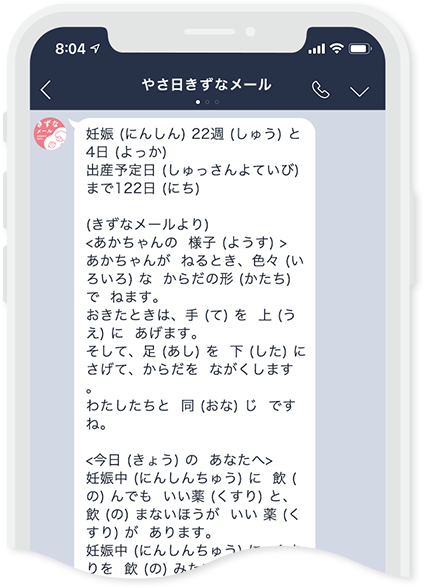

「きずなメール やさしい日本語版」は、

日本に住む外国人の方を対象に、

孤育てを防ぐセーフティネット強化を目的として

2020年11月から制作がはじまりました。

医療監修者と相談しながら「きずなメール」原文を短くし、それをやさしい日本語へ翻訳しました。

最終的な医療監修を行いました。仕上げにボランティアさんに協力頂き、原稿内の漢字にルビ(ふりがな)を振り、「きずなメール やさしい日本語版」が完成しました。

多くの方のご支援ご協力を得て、2022年2月、

ついに原稿が完成しました。

「きずなメール やさしい日本語版にほんごばん」

日本にほんに 住すむ外国人がいこくじんの みなさんへ。

LINEや メールから、やさしい日本語にほんごで

書かいた 情報じょうほうを 送おくります。